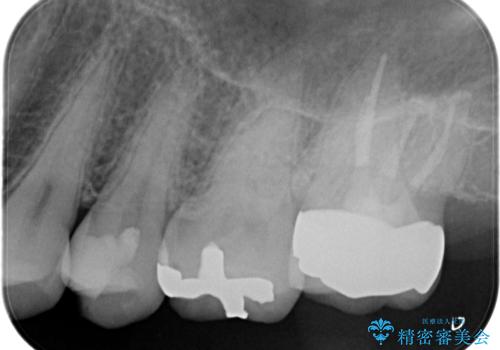

【セラミックインレー】虫歯の治療

- 定期検診にて虫歯を認めたため、セラミックインレーにて治療を行いました。

治療時にはラバーダムを装着しております。